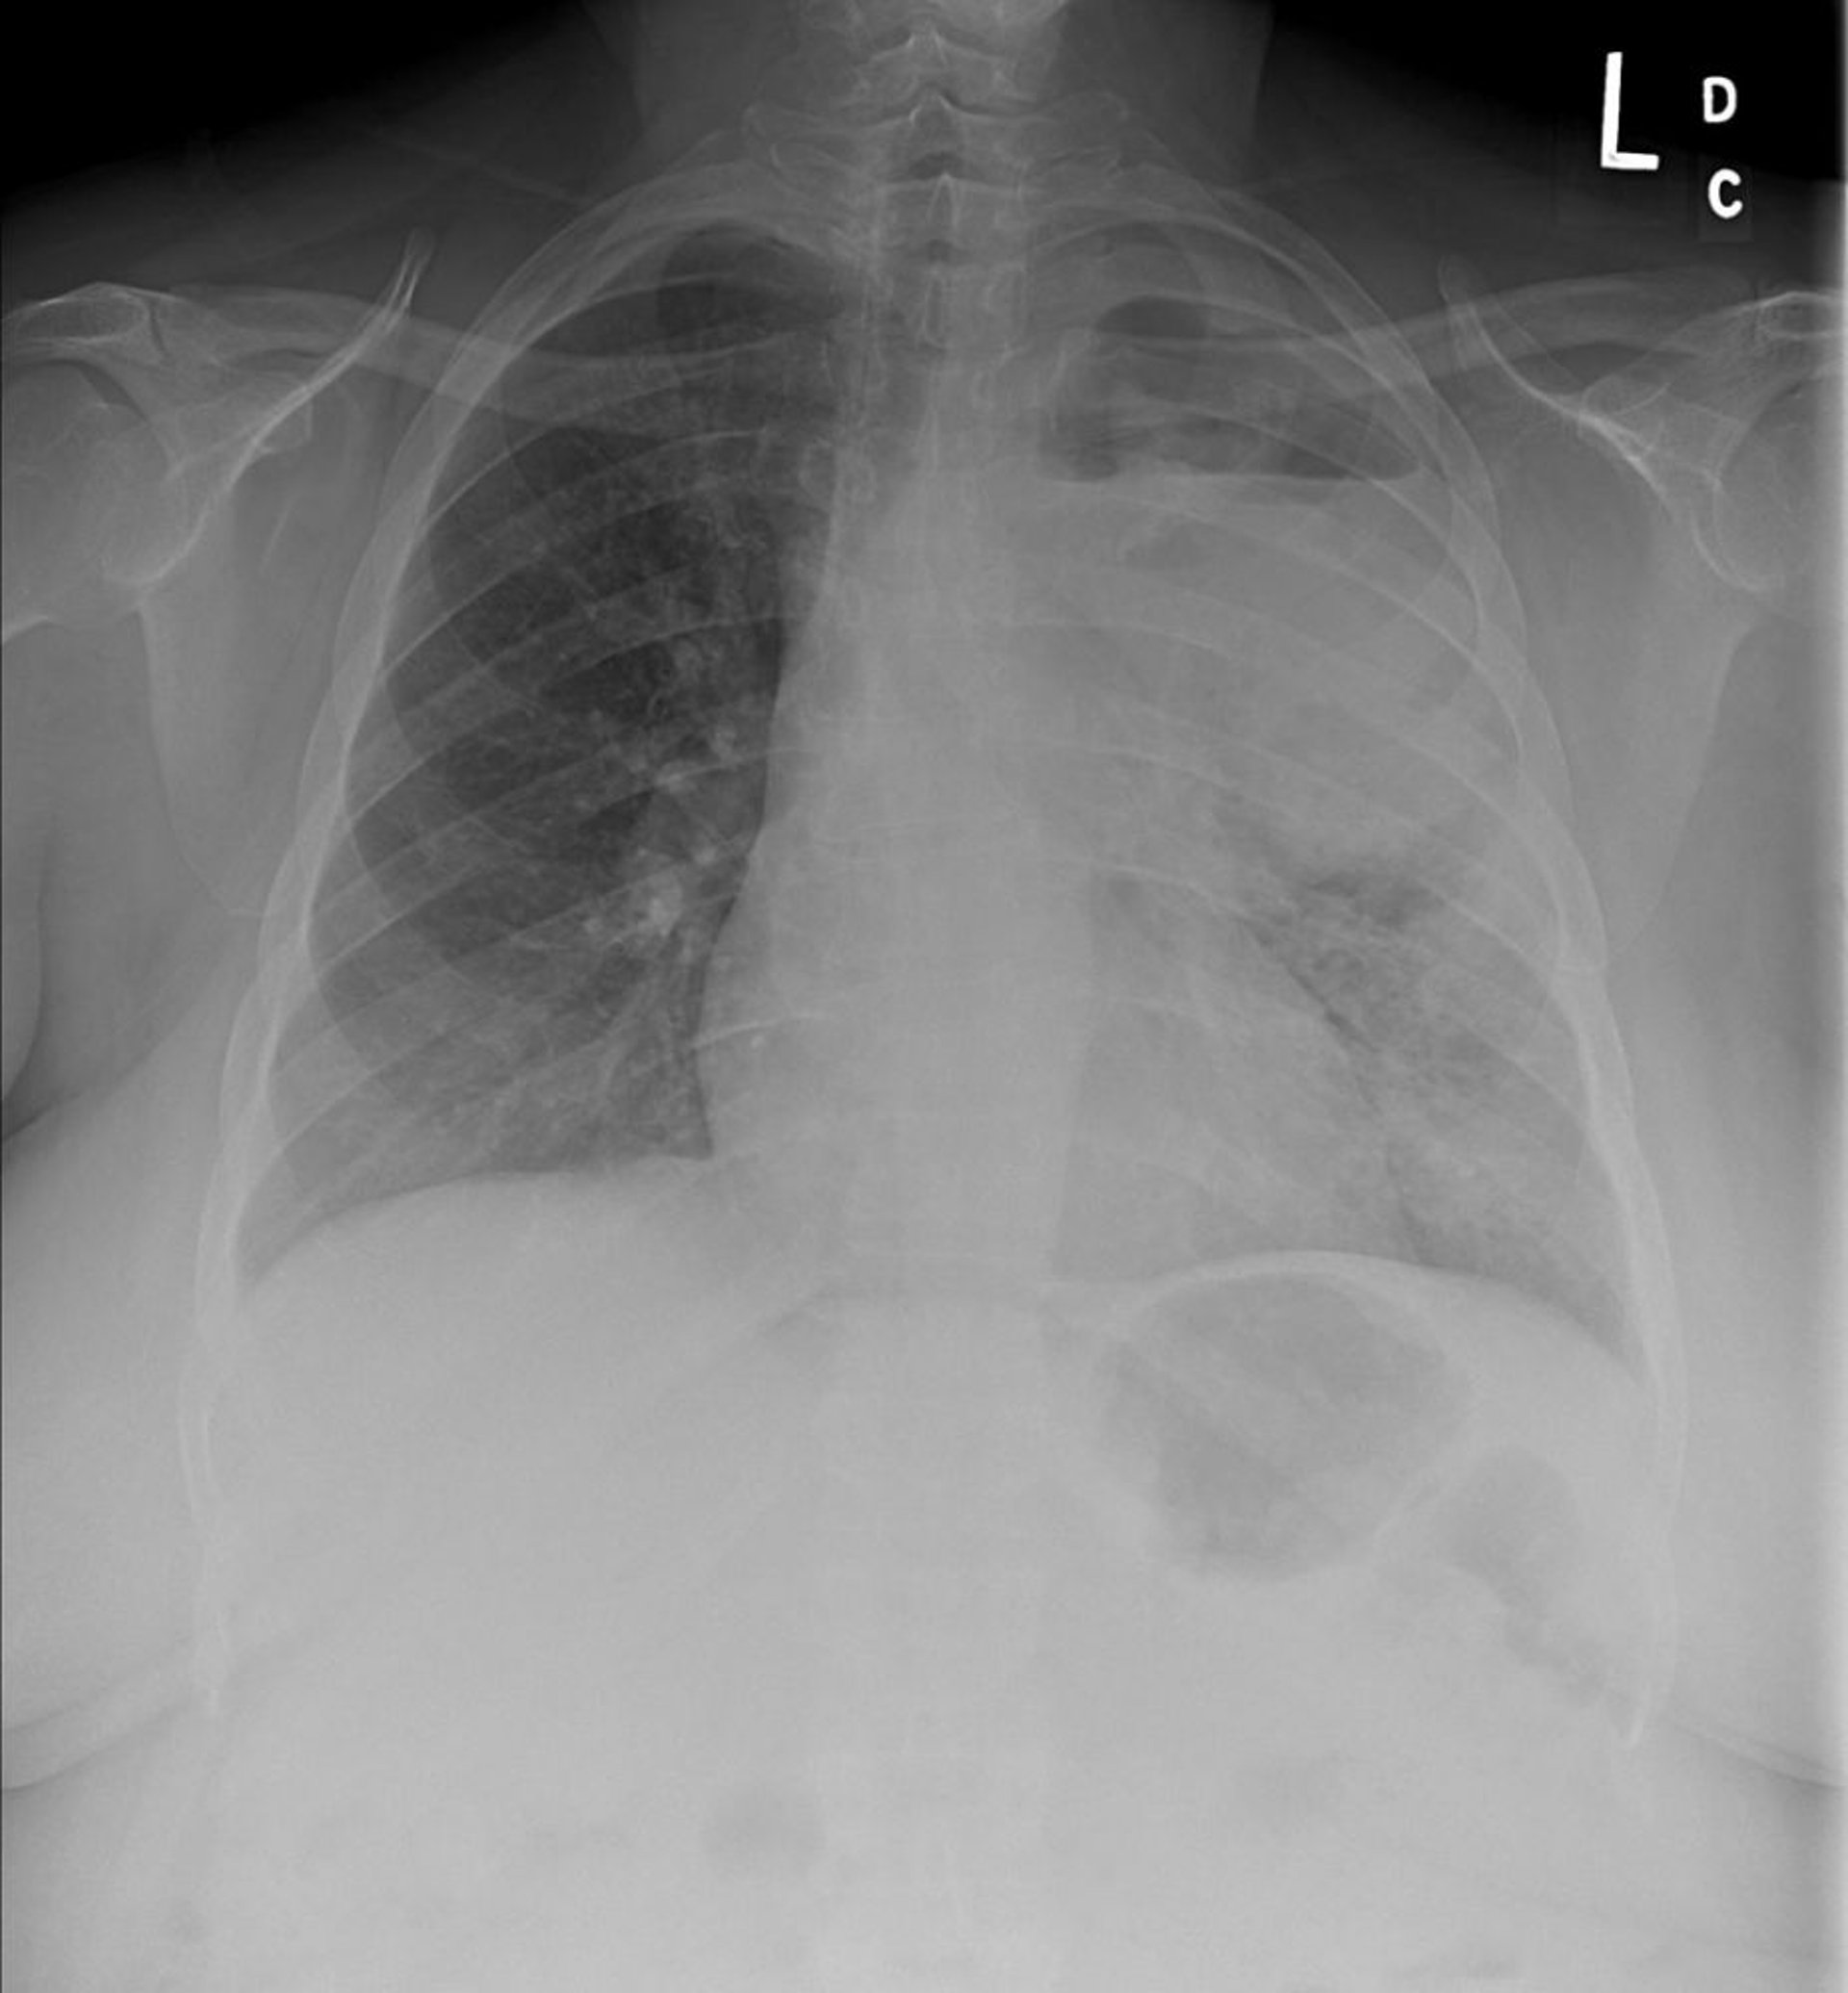

La radiographie de thorax montre un cancer du poumon non à petites cellules du lobe supérieur gauche avec une adénopathie médiastinale et hilaire gauche. La tumeur primitive est cavitée et un niveau air-liquide est présent.

Image courtoisie de Anne S. Tsao, MD.